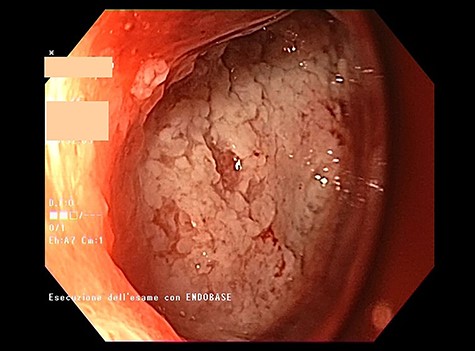

Endoscopic view of the prepyloric ulcer perforation (left) and intraluminal placement of E-VAC (right)

high PCR (291 mg/L) and the CT scan showed a right hydropneumothorax (Fig. 1). The first suspicion was an anastomotic leak and, in consideration of the hemodynamic instability and the severe septic state, the patient was submitted to emergency surgery. We performed a thoracoscopy with intraoperatively esophagogastroduodenoscopy which revealed a perforated prepyloric ulcer of the gastric tube. We therefore proceeded with accurate pleural toilette and closed the perforation with surgical stiches. At the end of the procedure, two thoracic drains and a naso-gastric tube with the distal end near the suture were placed. An additional naso-duodenum enteral feeding tube to ensure adequate nutrition was positioned. The patient was admitted in the Intensive Care Unit and supported with inotropic drugs, broad-spectrum antibiotics and proton pump inhibitor therapy. In the following days, the patient’s conditions improved allowing his extubation and his transfer to the surgical ward. Unfortunately, imaging and endoscopic check revealed a recurrent perforation. Considering the failure of the conservative approach, we decided to start the E-VAC Therapy on his 21st post-operative day (POD), using the Eso-SPONGE® System (B. Braun Surgical, S.A. Carretera De Terrassa, Rubi, Spain), firstly placed intraluminal because of the reduced size of the wall defect (Fig. 2). After three E-VAC replacements we did not observe any endoscopic or radiologic improvements. Moreover, on his 35th POD, due to a new impairment of vital signs, the patient underwent a second surgical treatment, with a new pleural toileting and another unsuccessful attempt of closing the conduit defect surgically. Considering the prolonged hospital stay, we placed a feeding jejunostomy. We proceeded with a new attempt of E-VAC, this time by placing it intracavitary (Fig. 3 and Fig. 4). The E-VAC was changed every 48–72 hours, reshaping the dimension of the sponge every time according to the size of the cavity. We observed a progressive reduction of the cavity size during the seriated endoscopic and CT evaluation. Considering the continuous improvement of patient’s clinical condition we discharged him after 84 days of hospitalization, with the E-VAC in place. The device replacement was carried on twice a week as an outpatient treatment, until its definitive removal (Fig. 5). The total duration of the therapy was 37 days with 13 E-VAC intracavitary interventions. Seven days after the device removal we performed an upper gastrointestinal X-Ray with oral contrast that showed no contrast medium leakage. The patient was therefore allowed to resume oral intake. At 6 months follow up the patient was in good clinical conditions; radiological test and endoscopy showed no abnormalities.